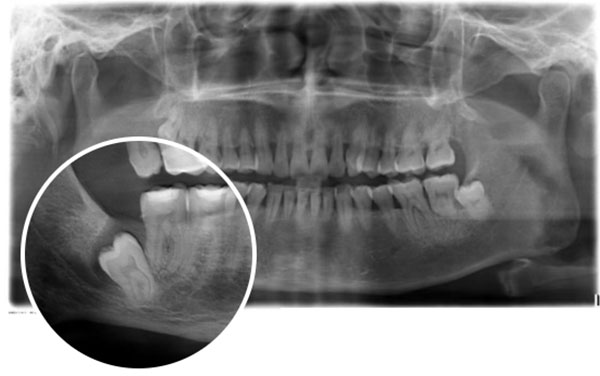

“片子显示智齿阻生,可一想到拔牙就腿软”

“不是所有的智齿都需要拔除,但阻生智齿、有症状或隐患的智齿,不仅影响口腔健康,还可能引发邻牙损伤、颌骨吸收等并发症,建议尽早处理。特别是癌症患者,很多肿瘤治疗药物会引发加重阻生智齿的相关并发症,还会影响口腔伤口愈合,所以如果有这类智齿,还是建议尽早拔除的。”吴斌提醒说,“我们就是要通过技术革新与服务升级,让患者告别传统拔牙的恐惧,真正实现‘无痛拔牙、快速康复’。”